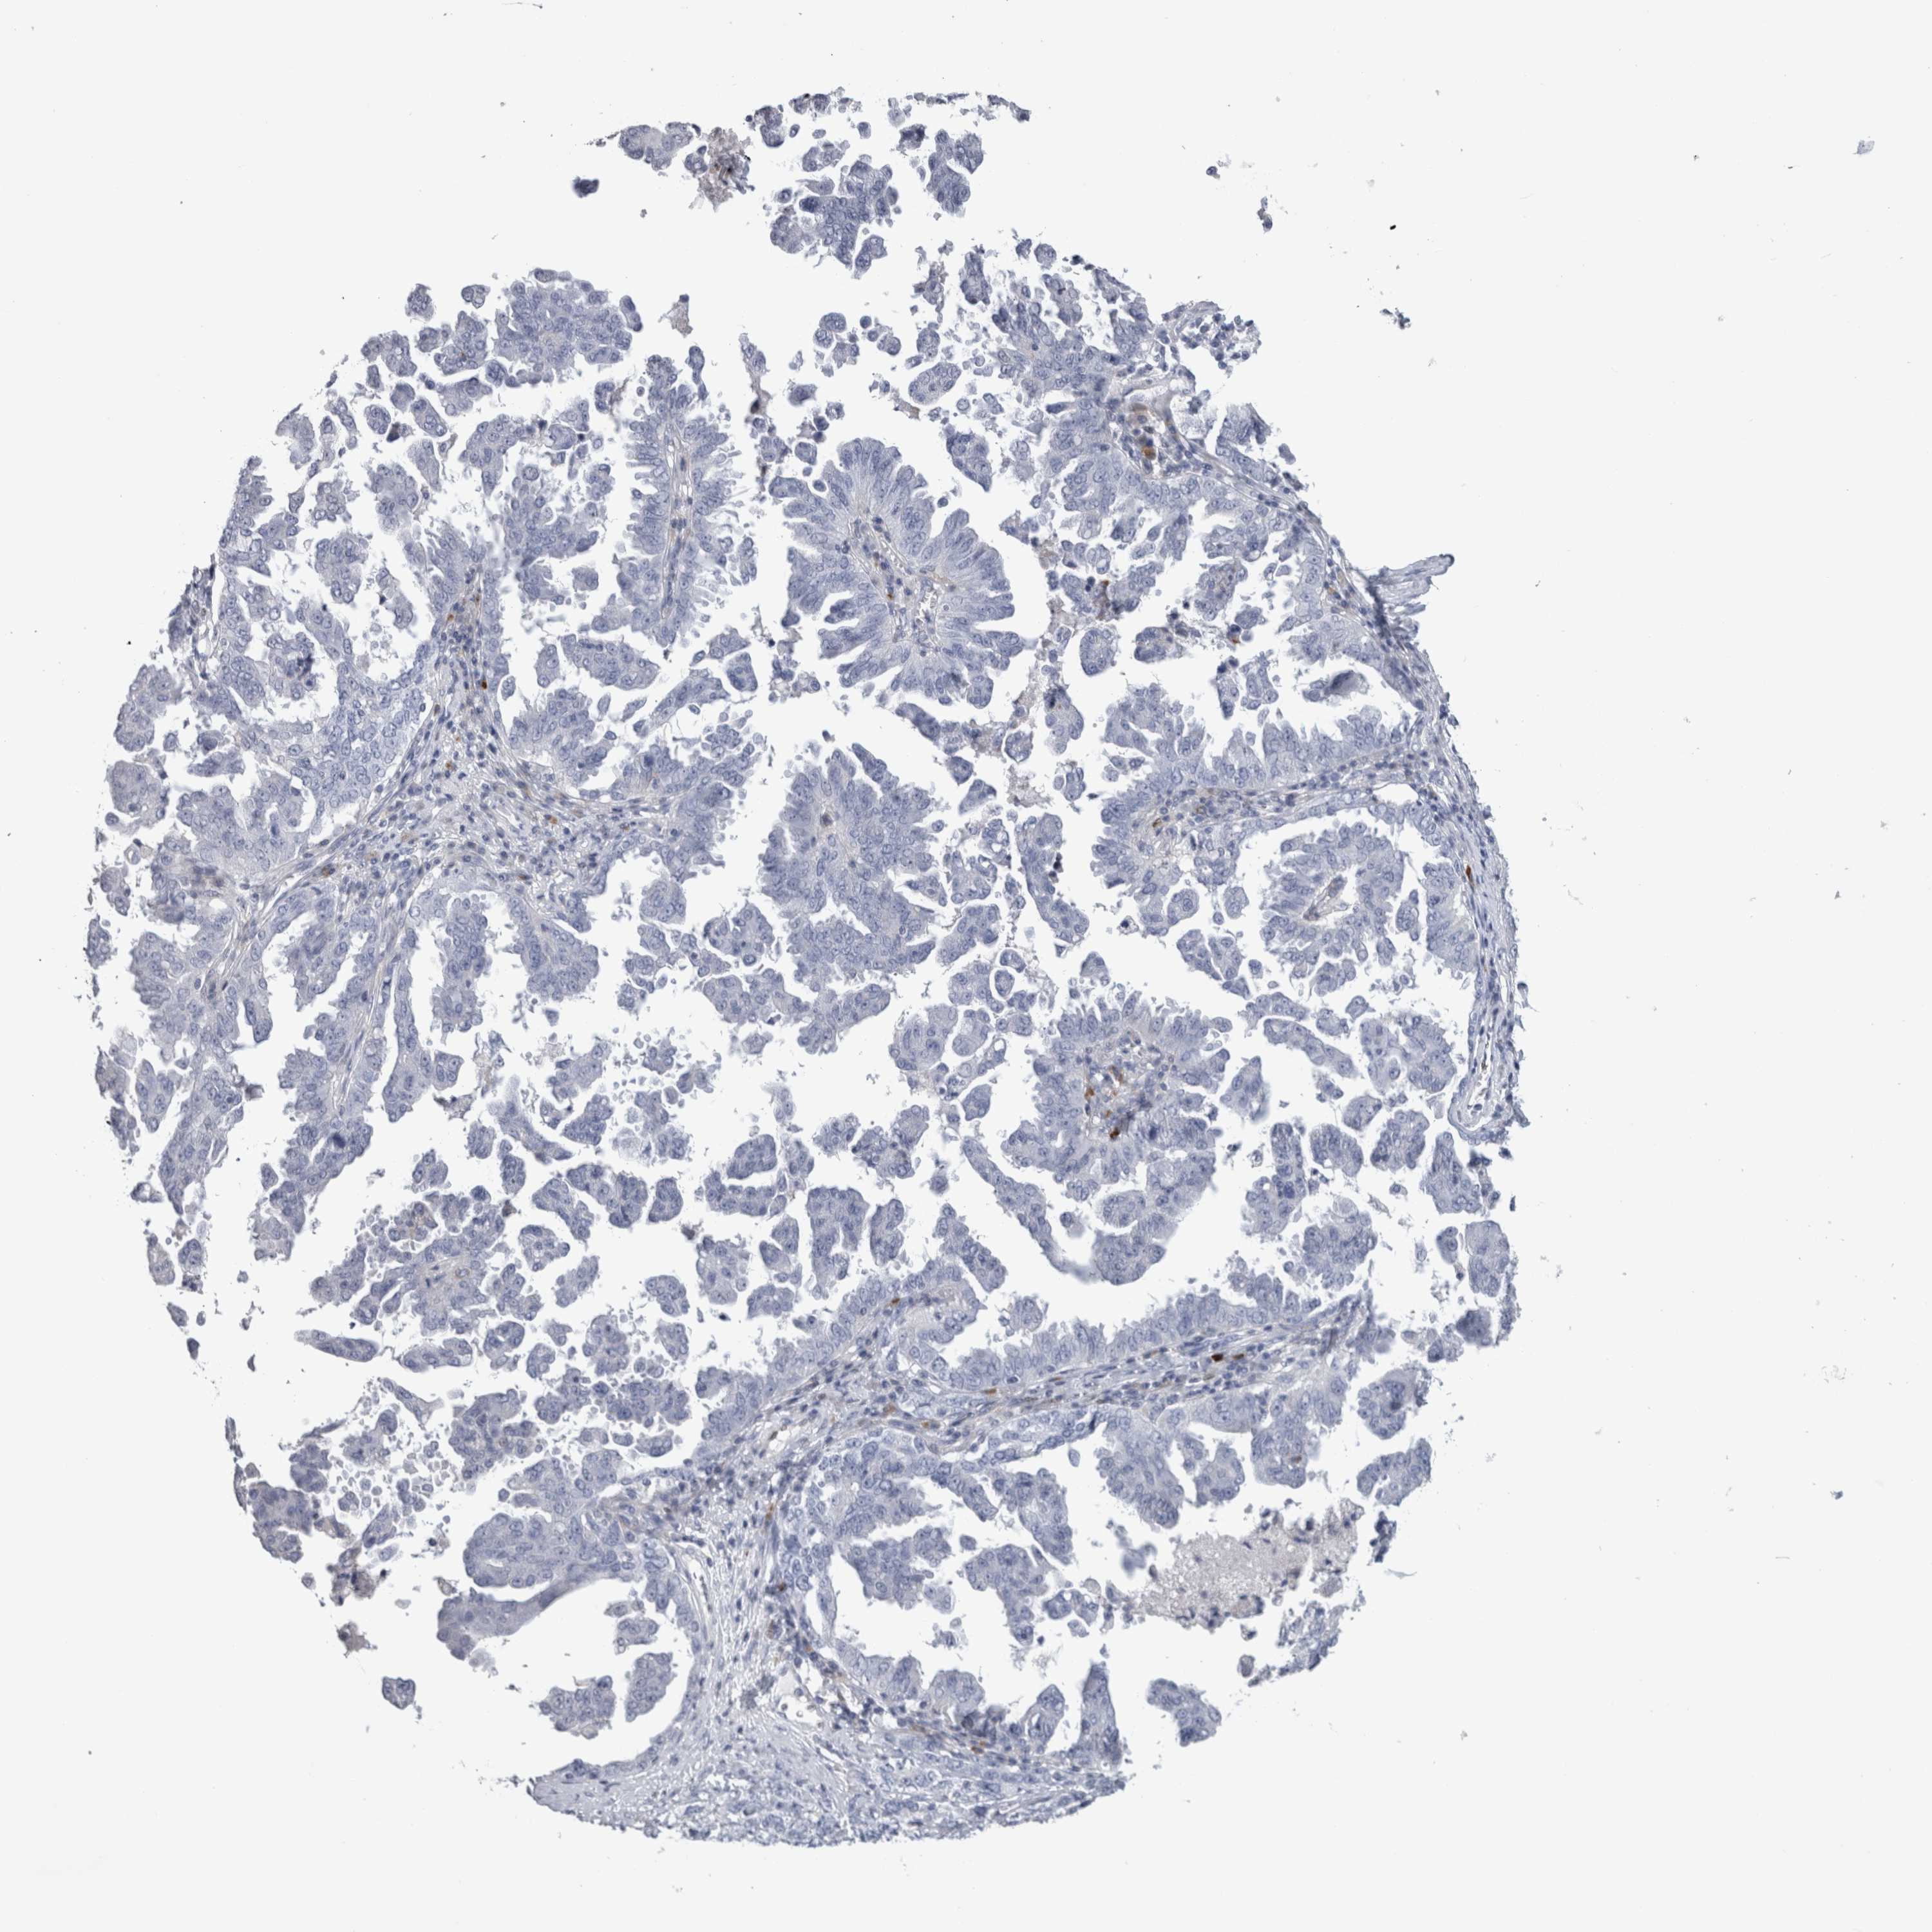

OVARIAN CANCER - Protein expressioni

A mouse-over function shows sample information and annotation data. Click on an image to view it in a full screen mode. Samples can be filtered based on level of antibody staining by selecting one or several of the following categories: high, medium, low and not detected. The assay and annotation is described here.

Note that samples used for immunohistochemistry by the Human Protein Atlas do not correspond to samples in the TCGA dataset.

Antibody stainingi

Antibody staining in the annotated cell types in the current human tissue is reported as not detected, low, medium, or high, based on conventional immunohistochemistry profiling in selected tissues. This score is based on the combination of the staining intensity and fraction of stained cells.

Each image is clickable and will lead to virtual microscopy that enables deeper exploration of all samples and also displays staining intensity scores, fraction scores and subcellular localization as well as patient and tissue information for each sample.

Antibody HPA024426

Antibody CAB007057

Cystadenocarcinoma, serous, NOS

Carcinoma, endometroid

Cystadenocarcinoma, mucinous, NOS

Carcinoma, NOS